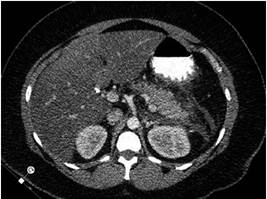

Posteriormente, se procedió a realizar tomografía axial computarizada (TAC) de abdomen contrastada (Figuras 1 y 2) que reportó pancreatitis Baltazar D, permitiendo la reestratificación a pancreatitis Marshall 1 Baltazar D, APACHE-II: 20 (mortalidad: 35%) con criterios de pancreatitis severa e indicación de traslado a la unidad de cuidados intensivos (UCI). Adicionalmente, se complementaron los estudios con perfil metabólico para aclarar la etología con resultados de TAG en 18 060 mg/dL y hemoglobina glucosilada (HbA1c) en 9,87.